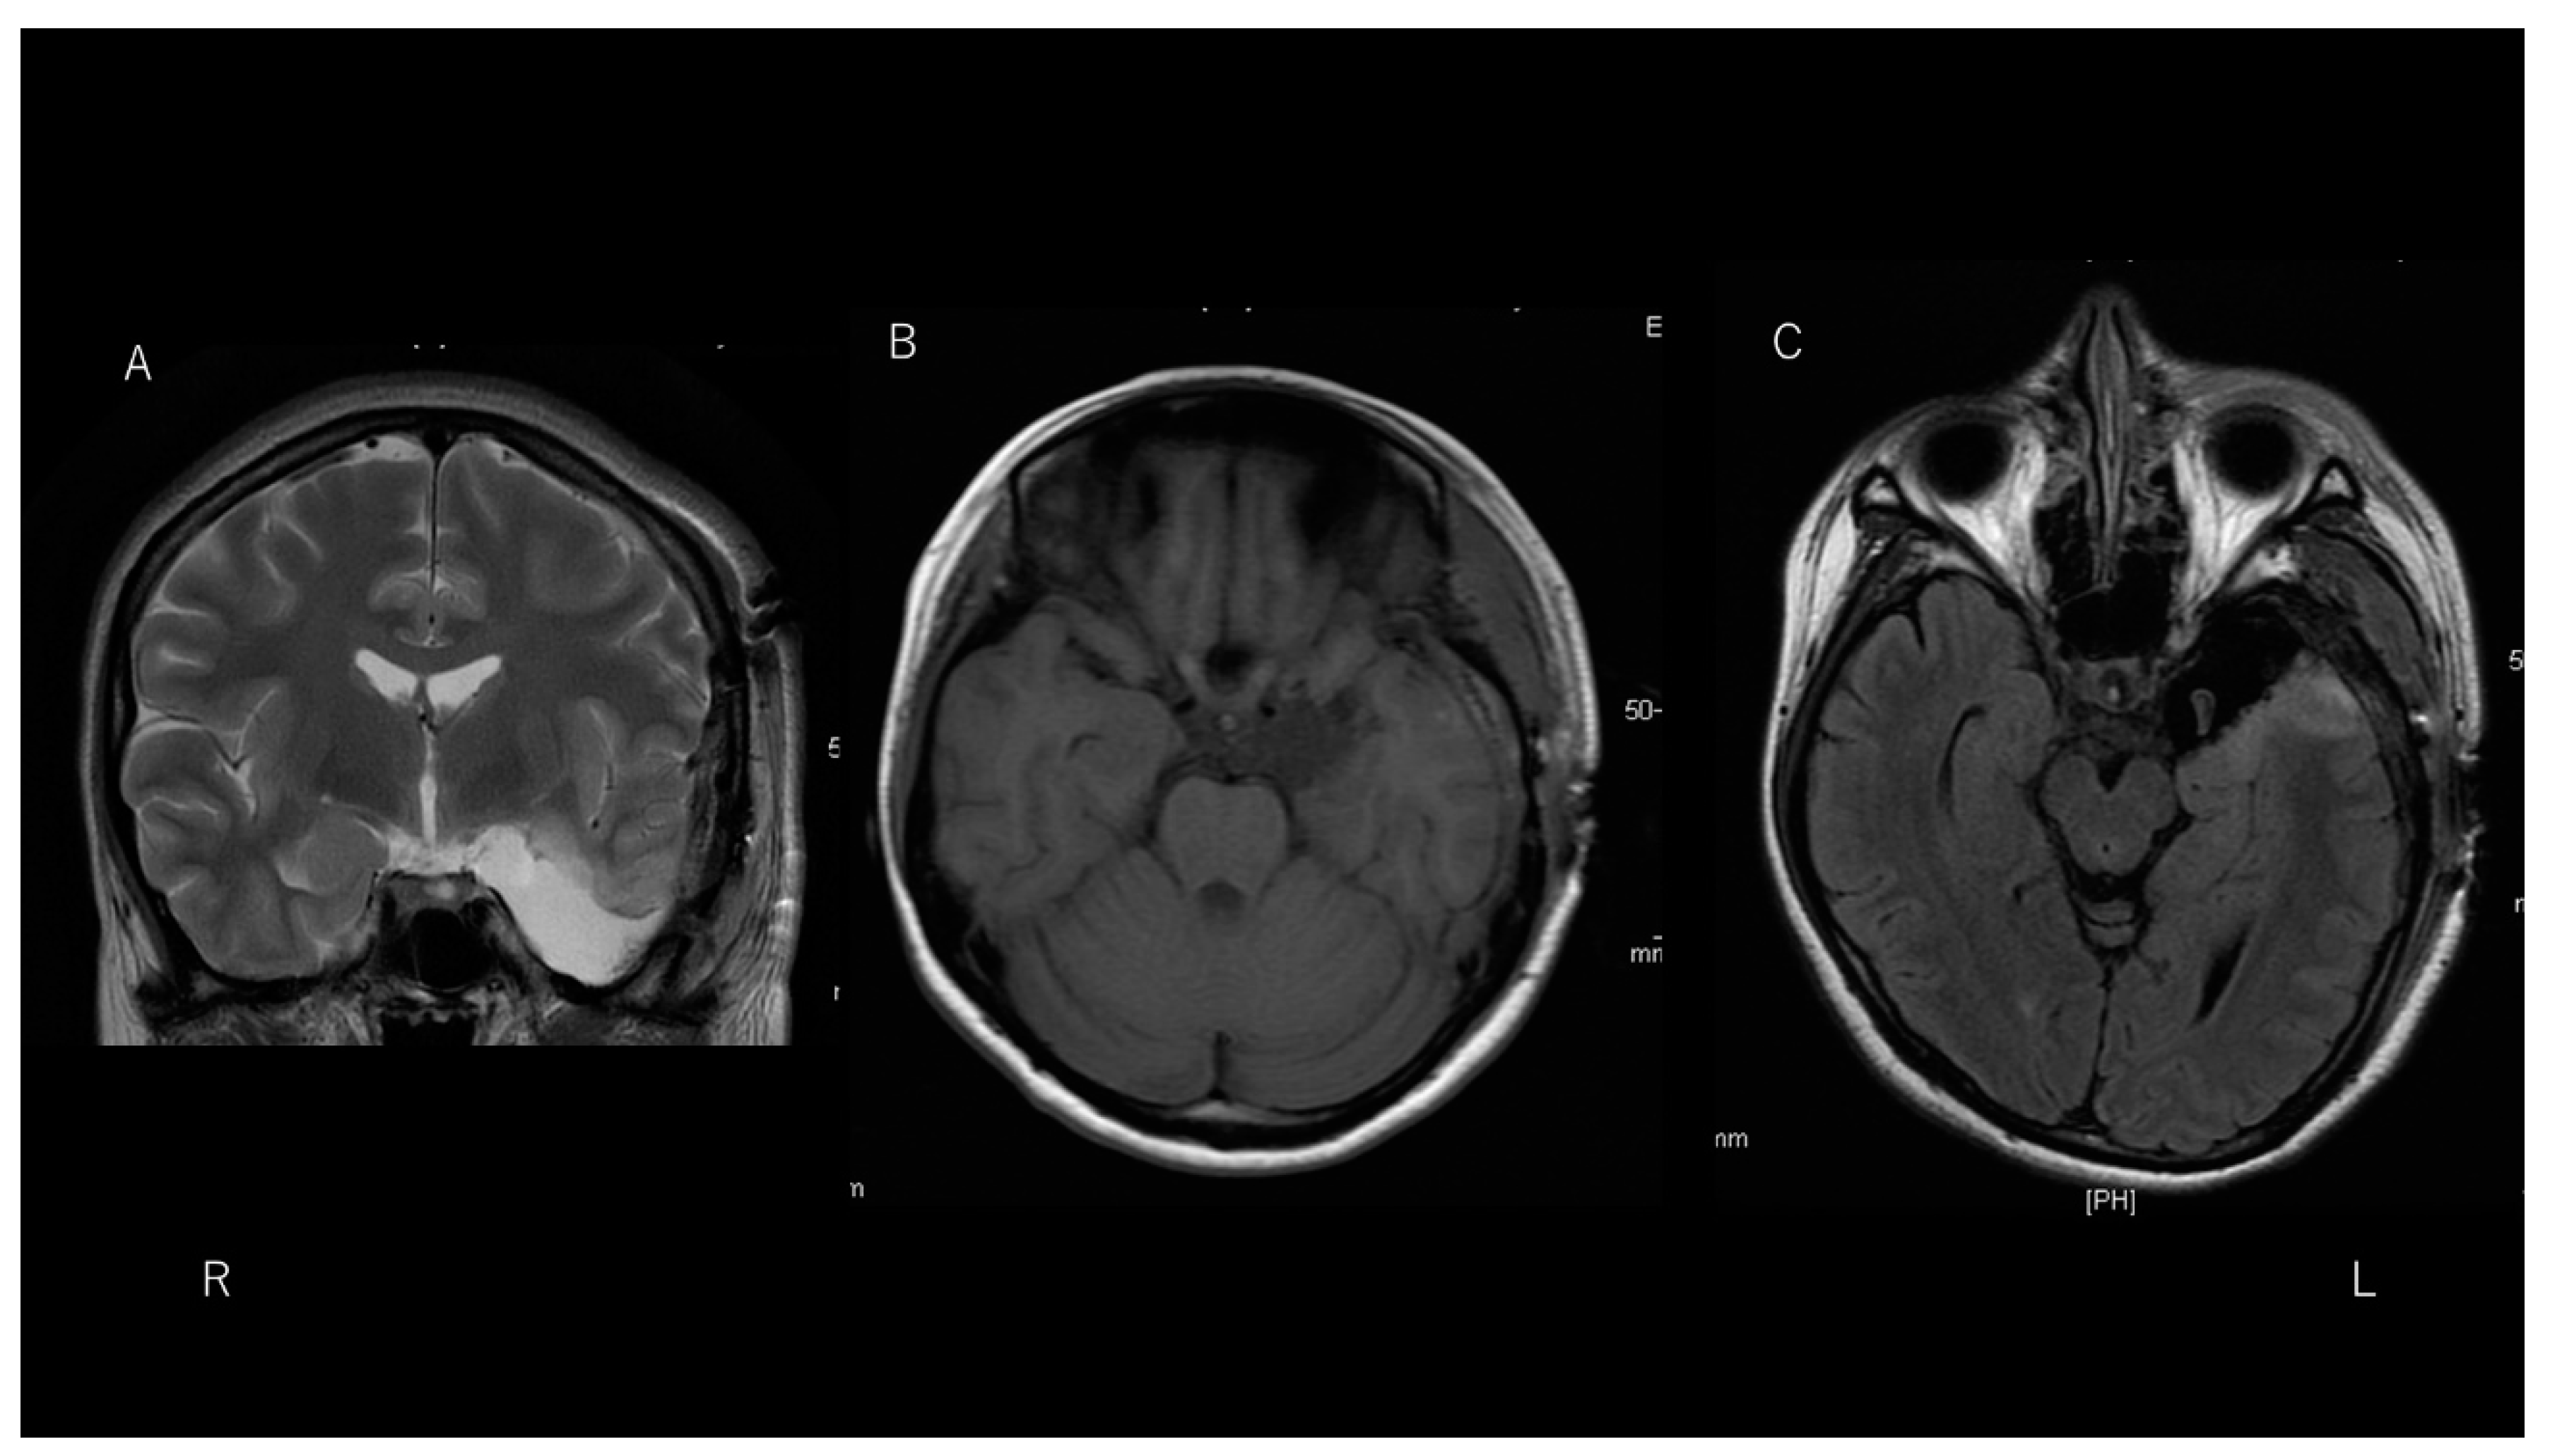

Following excision of the tip of the left temporal lobe, which included the cystic lesion, the patient remained free from daily olfactory auras as well as focal-onset impaired awareness seizures and focal-to-bilateral tonic-clonic seizures for more than 50 days. Post-operative MRI depicted total removal of the lesion with the tip of the left temporal lobe (Figure 4). Post-operative scalp EEG showed no focal slowing and epileptiform discharges observed, even though a continuous breach rhythm was seen in the left fronto-temporal area.

Figure 4. T2-weighted imaging (A) and T1-weighted imaging (B) reveal total removal of the lesion in the left temporal region. Fluid-attenuated inversion recovery imaging (C) of a hippocampus slice shows removal of the anterior temporal lobe tip, preserving the hippocampus.